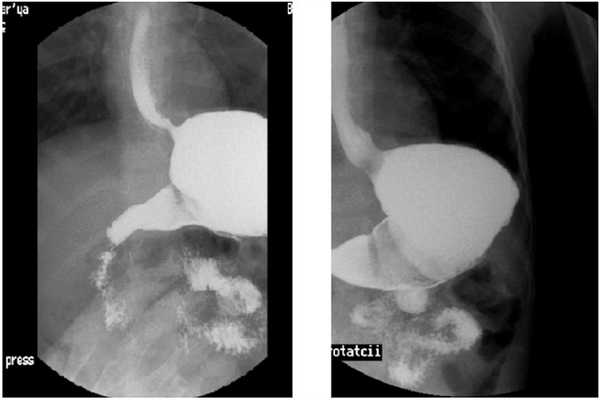

Далее выполняется осмотр желудка, двенадцатиперстной кишки (ДПК): оценивается анатомия и топография, скорость эвакуации из желудка, скорость пробега по ДПК, наличие препятствий пассажу, дискинезии, проводится пальпация, для ускорения пассажа и как провоцирующий фактор.

Провокационные пробы включают в себя ротацию пациента, умеренное давление на живот, напряжение мышц живота (кашель, натуживание, приподнимание пациентом ног). Положительной (у младенцев) считается проба, при которой в результате давления на живот в течении 30 сек. и сразу после этого отмечается, как минимум, два эпизода заброса контрастного вещества из желудка в пищевод. При этом рвота в расчёт не принимается. Рвота: сложный рефлекторный акт, характеризующийся сокращением желудка, раскрытием нижнего и верхнего пищеводных сфинктеров с выбросом контраста наружу.

Следующий этап, при отрицательных результатах выше выполненных манипуляций, постановка водно-сифонной пробы.

Пациент укладывается на спину в положении на правом боку под углом 450 [2], указание на методику, предложенную Linsman в 1965 г.). Положительным считается проба, при которой происходит заброс содержимого желудка в пищевод. При этом можно осуществлять маятникообразные умеренные надавливания на переднюю брюшную стенку, для оценки состояния средне пищеводного сфинктера [3, 4, 5].

Высока значимость водно-сифоной пробы (ВСП), при установлении ГЭР. Из 50 обследованных детей по поводу ГЭР, заброс без ВСП регистрировался у 19-и (методика Singleton - контраст вводится в расчёте 1/3 от разового кормления), и у 32-х, при выполнении ВСП [2].